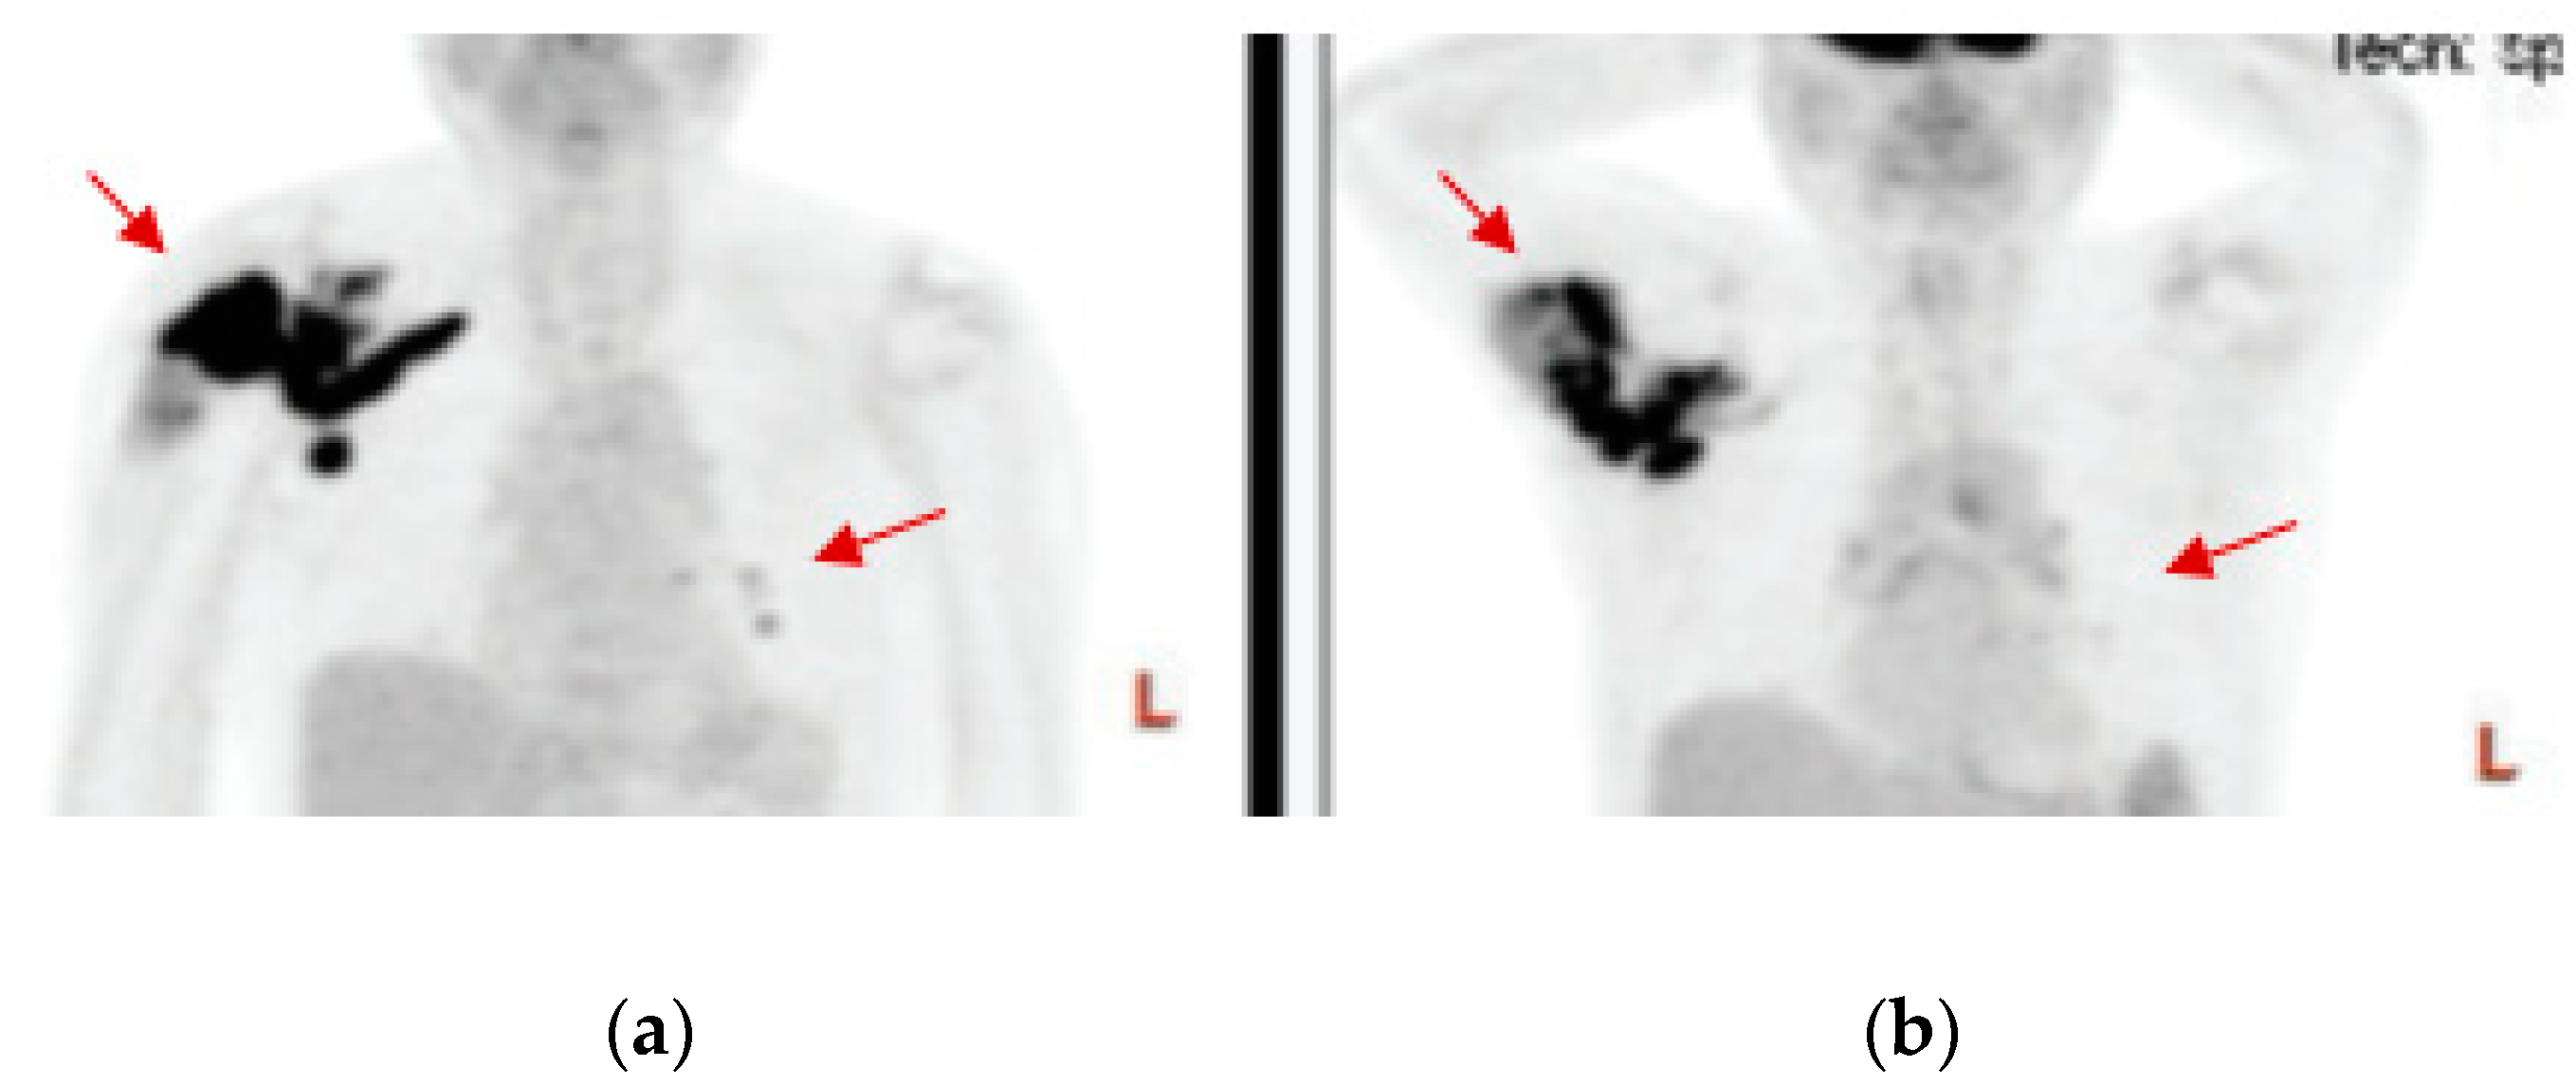

- Mori, Y.; Kinoshita, S.; Kanamori, T.; Kataoka, H.; Joh, T.; Iida, S.; Takemoto, M.; Kondo, M.; Kuroda, J.; Komatsu, H. The Successful Treatment of Metastatic Extraosseous Ewing Sarcoma with Pazopanib. Intern. Med. 2018, 57, 2753–2757. [Google Scholar] [CrossRef]